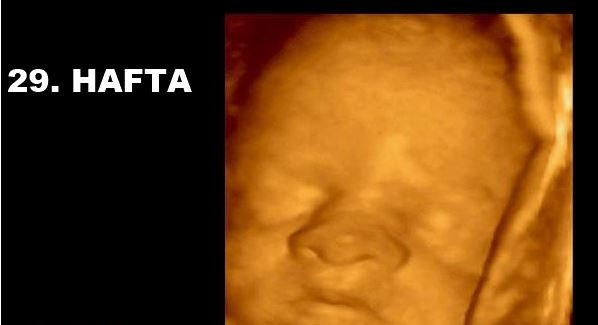

gebelikte 3 ve 4 boyutlu ultrason